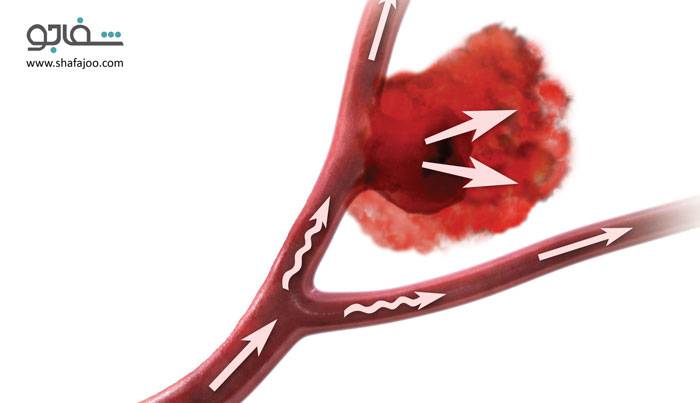

آنوریسم - Aneurysm

| آنوریسم عبارت است از بزرگ شدن یا بیرونزدگی دیواره یک سرخرگ در اثر ضعف دیواره سرخرگ. آنوریسم اغلب پس از حمله قلبی رخ میدهد و معمولاً در آئورت (سرخرگ بزرگی که از قلب منشاء گرفته و در سینه و شکم به سمت پایین حرکت میکند) یا سرخرگهایی که مغز، پاها، یا دیواره قلب را تغذیه میکنند، ایجاد میشود. |